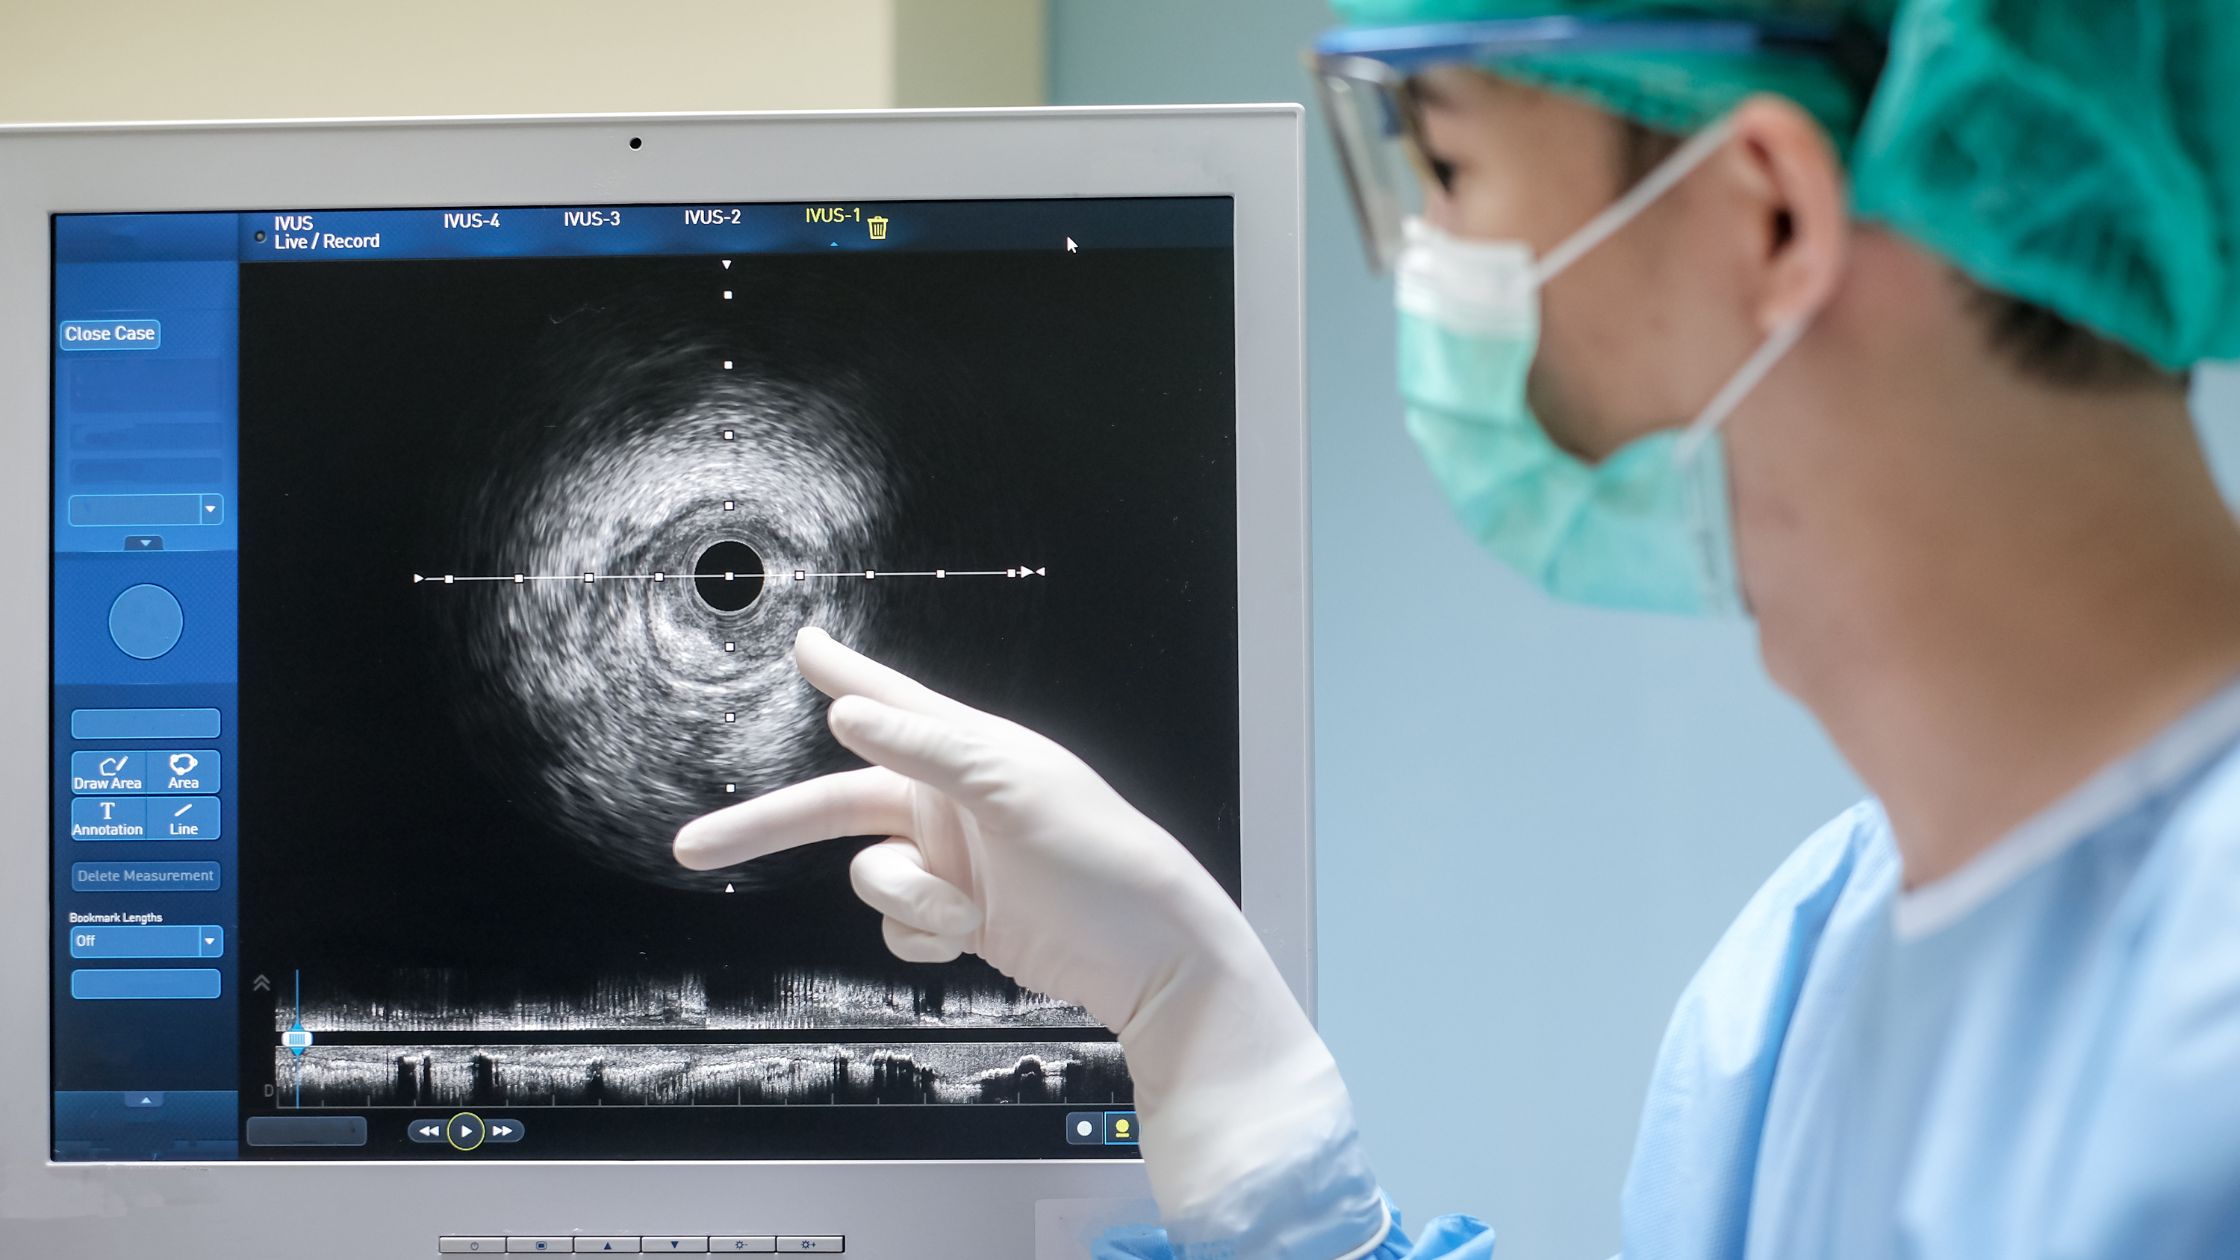

صور عيادة د/ إبراهيم الشال